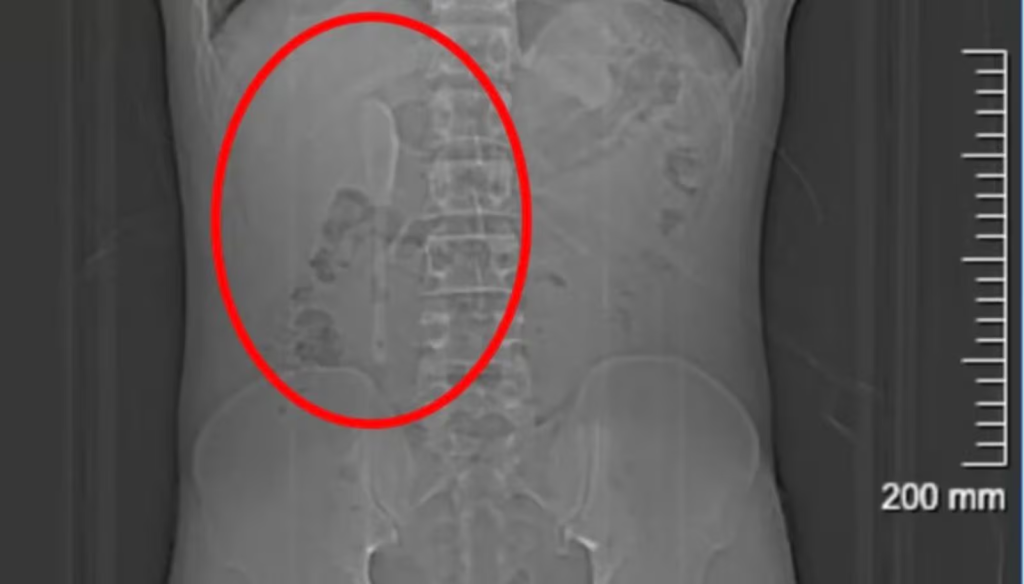

Mesmo com a colher dentro do corpo, ele seguiu com sua rotina normalmente pelos cinco meses seguintes, sem apresentar sintomas significativos. Só procurou ajuda médica em junho, após suspeitar que havia engolido plástico ao comer comida de delivery. Foi então que exames revelaram o verdadeiro problema: uma colher de 15 centímetros presa em uma posição delicada no intestino.

Segundo os médicos, a retirada foi desafiadora devido à superfície escorregadia do utensílio e ao risco de perfuração intestinal. A cirurgia endoscópica, que durou cerca de nove horas, exigiu o uso de dois tipos de pinças para puxar o objeto de volta ao estômago antes da remoção completa.